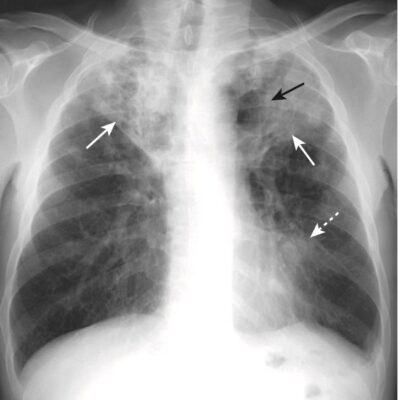

- Bệnh khoang chứa khí có thể biểu hiện dấu bóng bờ (dấu xoá bờ – silhouette sign) (Hình 4).

- Dấu xoá bờ xảy ra khi hai cấu trúc có cùng mật độ X quang (chẳng hạn như nước và mô mềm) chạm vào nhau sao cho rìa hoặc bờ giữa chúng biến mất. Không thể nói cấu trúc này này bắt đầu ở đâu và cấu trúc kia kết thúc ở đâu. Dấu hiệu bóng bờ không chỉ có giá trị ở ngực mà còn hỗ trợ cho việc phân tích các nghiên cứu hình ảnh ở những vị trí khác.